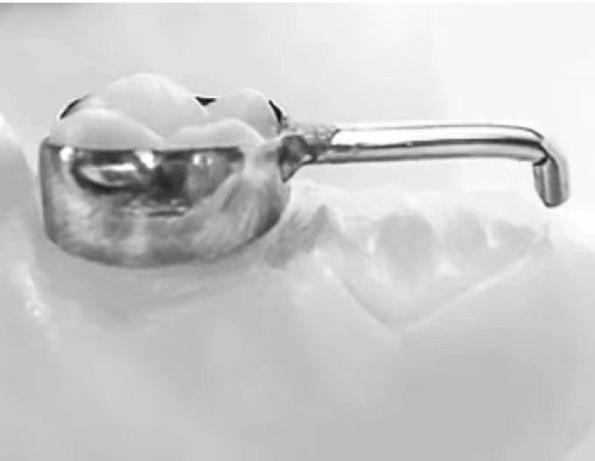

带环或全冠丝圈式间隙保持器

主要适用于单侧单颗乳磨牙早失的治疗。